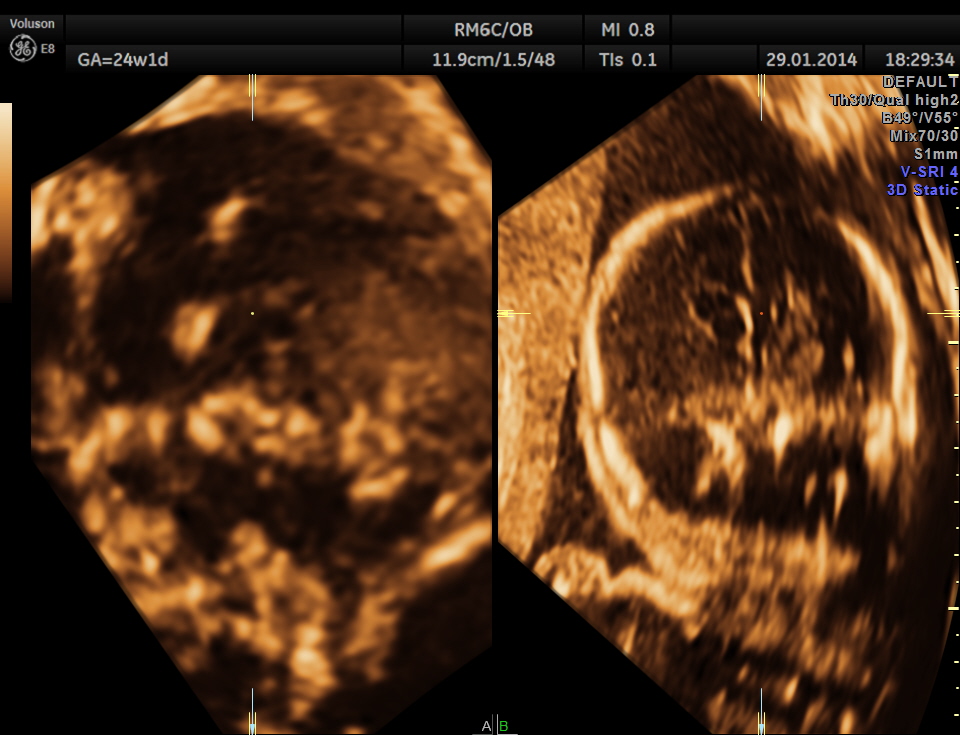

This was a 32-year-old lady – primi gravida . She was referred for an anomaly scan around 24 weeks gestation.Her earlier scan done in the first trimester elsewhere was reported as normal.

The following images were obtained. Unilateral choroid plexus cyst was seen .